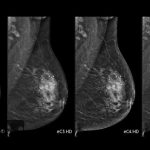

ماموگرافی چیست؟

ماموگرافی یک روش تصویربرداری تشخیصی است که با استفاده از دوز کم اشعه ایکس، تصاویر دقیقی از بافت پستان ارائه میدهد. این روش، برای تشخیص زودهنگام سرطان سینه و بررسی تودههای مشکوک در مراحل اولیه کاربرد دارد.

- امکان ماموگرافی سهبعدی برای مشاهده دقیقتر جزئیات